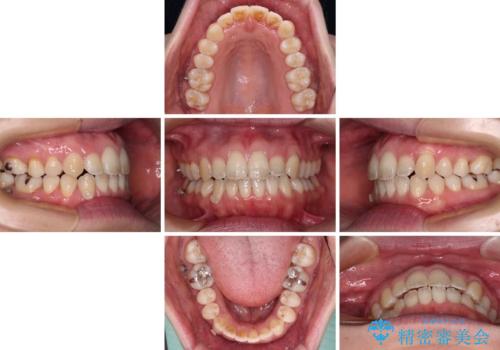

- 受け口傾向でクロスバイトの前歯を治したいとのことで来院された患者様です。

下顎骨が若干左側に変位していたため、右側にアンカースクリューを使用し、積極的に移動させながらインビザラインにて矯正治療を行うこととしました。

インビザラインによる矯正治療は、受け口傾向の治療に非常に適した方法であり、事前にシミュレーションに沿って治療を進めることできます。

今回の治療では骨格的な偏位があったためアンカースクリューを使用し、より確率の高い治療を行うことができました。